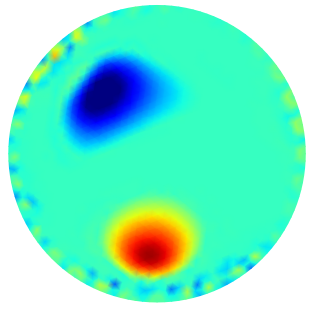

In Fig.4 we show some sample conductivity reconstructions and we report below the corresponding PSNR evaluation. For each sample, the first column represents the estimated support pre-computed by the Oracle-Net together with the FN value associated, the second column illustrates the target ground truth (GT) reconstruction, and from the third to the sixth columns the computed reconstructions are shown for the different algorithms together with the PSNR values obtained. From a visual inspection of the illustrated results and from the PSNR values reported, we can observe the benefit of incorporating the Oracle-Net estimated support into the PGM algorithmic framework. PGM-TV and PGM- achieve lower performance than their Oracle-Net-based counterparts. Moreover, the use of the TV regularizer seems to be beneficial with or without Oracle exploitation.

In Fig.5 some conductivity reconstructions are illustrated. The collected voltage has been corrupted by adding a realization of random noise with Gaussian distribution and noise level (added noise is such that the intrinsic SNR is 40dB). We observe that, even though the Oracle-Net was trained on noiseless data, the mask obtained in inference with noise measurements - Fig.5 first column - is sufficiently accurate, and PGM algorithm performs very well on the noise measurements. A natural consequence of having noise-corrupted measurements is the degradation in the conductivity reconstruction. Comparing the results in the third columns of Fig.4 and Fig.5 we observe quantitatively a degradation in the performance of reconstructions in terms of PSNR values. Analogous behavior can be observed comparing the fourth columns of Fig. 4 and Fig. 5, which have been obtained without taking advantage of the contribution of the Oracle Mask.